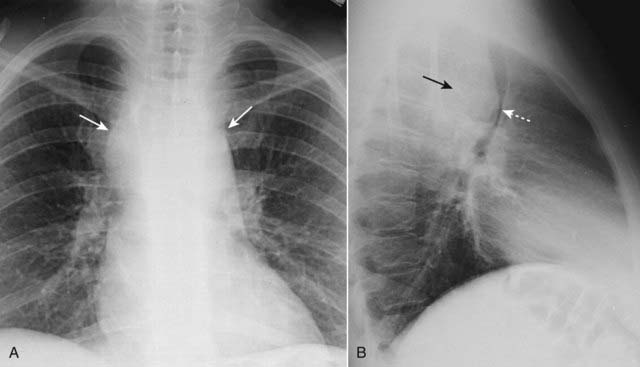

Figure 12-18 Bronchogenic carcinoma with hilar and mediastinal adenopathy.

A peripheral lung mass (solid black arrow) shows evidence of ipsilateral hilar and mediastinal adenopathy (solid white arrows) and contralateral mediastinal adenopathy (dotted white arrow). Bronchogenic carcinoma may present with metastatic lesions that can manifest in distant organs or in the thorax itself. This was an adenocarcinoma of the lung.

image Hilar adenopathy. Usually unilateral on the same side as the tumor (Fig. 12-18).

image Pleural effusion. Frequently, there is associated lymphangitic spread of tumor when there is a pleural effusion.